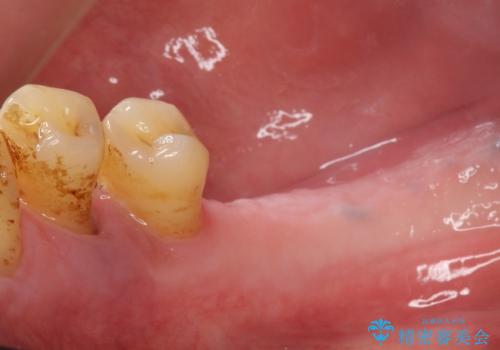

再生療法と骨外科処置により、歯周ポケットは全周2mm以下に改善されました。

保存が難しいと思われた歯を残すことができ、患者様にご満足頂けました。

歯周病治療と連結補綴により歯の動揺がなくなり、「なんでも食べられます!」と喜んで下さいました。